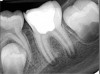

Fig 11. Preoperative radiograph. Courtesy of Dr. Guillaume Jouanny.

Figure 11

Fig 12. Postoperative radiography after full pulpotomy was performed. Courtesy of Dr. Guillaume Jouanny.

Figure 12

Case 2: Pulpotomy

In this case, the tooth tested vital but showed clinical signs of irreversible pulpitis. Treatment with a full pulpotomy was chosen to improve the chances the remaining pulp would survive and remain healthy. The preoperative radiograph in Figure 11 shows extensive caries in the tooth and a slightly widened apical periodontal ligament. A full pulpotomy was performed using the BC putty (Figure 12). After the putty set, a coronal restoration was placed, and an immediate postoperative radiograph was taken and viewed. At the 1-year follow-up, the tooth was asymptomatic, and the radiograph showed continued root development (Figure 13), a healthy apical periodontium, and, importantly, no calcifications in the remaining pulp (as is often seen with a calcium hydroxide therapy). A radiograph taken of the contra-lateral tooth showed similar root development (Figure 14).